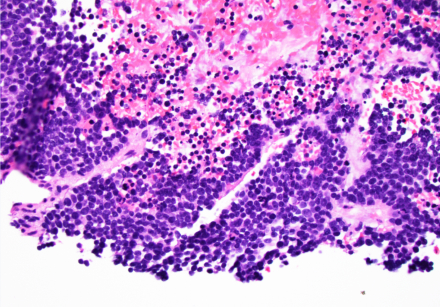

Hypertension was treated with amlodipine, labetalol, and spironolactone. Hypercortisolism was treated with metyrapone. Cortisol dropped from 182 to 4 ug/dL and BP improved to 120s-170s/60s-80s. Hyperglycemia was controlled with insulin. Biopsy results of the left retroperitoneal mass and right cervical lymph node were consistent with SCLC. She was started on palliative chemotherapy with carboplatin and etoposide.